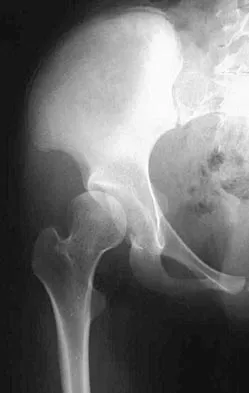

Figures 9a and 9b show the radiographs of a 12-year-old girl who has had right hip pain for the past 4 months. She reports that the pain is so severe that she is unable to walk and is now using a wheelchair. Examination reveals pain with any attempted range of motion. Management should include

Explanation

In addition to mild hip dysplasia, the radiograph shows an osteoblastic lesion of the right ilium. The patient's symptoms are much more severe than is typical for late hip dysplasia. MRI can determine the extent of the lesion in the bone and soft tissues. Following work-up and biopsy, the patient was diagnosed with Ewing's sarcoma. Springfield DS, Gebhardt MC: Bone and soft tissue tumors, in Morrissy RT, Weinstein SL (eds): Lovell and Winter's Pediatric Orthopaedics, ed 5. Philadelphia, PA, Lippincott Williams and Wilkins, 2001, pp 507-518, 542-544.